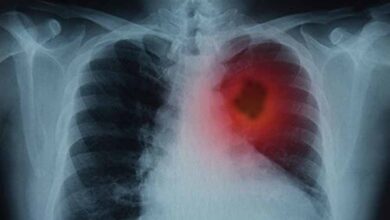

कैंसर उपचार में क्रांतिकारी खोज: वैज्ञानिकों ने फेफड़ों के ट्यूमर घटाने का नया तरीका विकसित किया